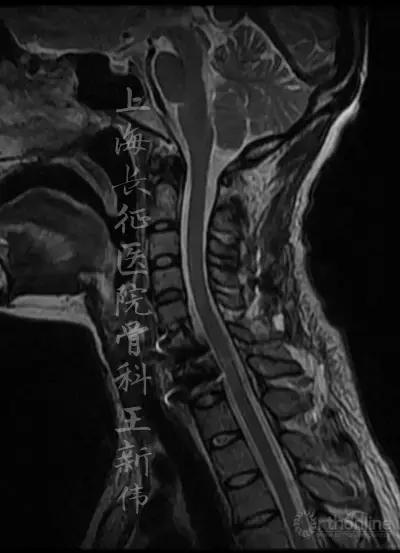

颈椎MRI平扫:

第二次术前颈椎MRI平扫,可见C6/7存在成角畸形,脊髓受压